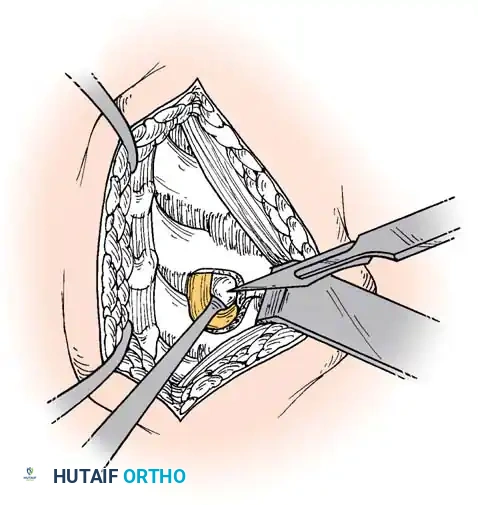

Step 2: Annulotomy and Discectomy

Self-retaining retractors are placed beneath the elevated medial borders of the longus colli. A rectangular annulotomy is performed using a #11 blade. The disc material is systematically removed using pituitary rongeurs and curettes.

Step 3: Decompression

The posterior longitudinal ligament (PLL) is carefully identified and often resected to ensure no extruded disc fragments remain in the epidural space. High-speed burrs and Kerrison rongeurs are utilized to resect posterior osteophytes and decompress the uncinate processes bilaterally, ensuring the exiting nerve roots are entirely free.